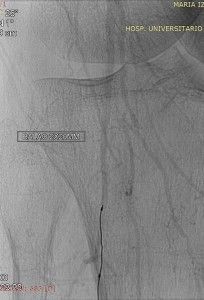

Após a punção um guia 014 300 cm foi introduzido e tentou-se vencer a obstrução do sentido distal para o proximal (retrógrado). Esta manobra também foi infrutífera devido ao alto grau de calcificação arterial. Um balão de angioplastia foi então introduzido para dar suporte ao guia e desta vez consegui-se ultrapassar o segmento ocluído conforme evidenciado na foto abaixo.

Após ultrapassar a oclusão, o guia foi capturado por alça de captura inserida pela introdutor 5F implantado na Femoral direita e assim exteriorizado através deste.